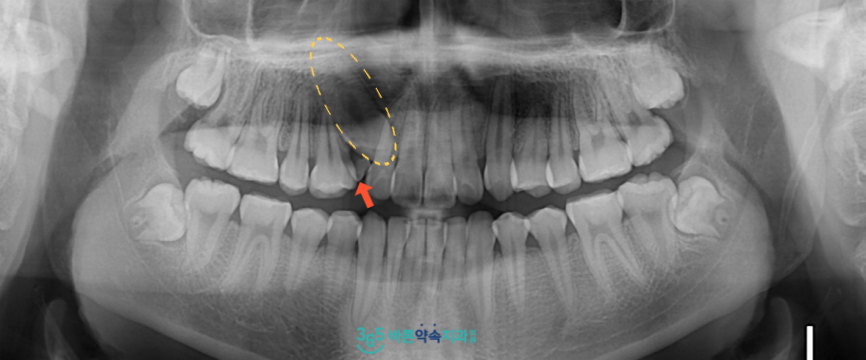

먼저 구강 내에서

확인해 보았더니

빨간색 화살표 표시의

위턱 오른쪽 유 견치(#43)가

남아 있는 것을 확인할 수 있었는데요.

정밀한 검사를 위해

파노라마 사진을 촬영해 보았더니

노란색 동그라미 표시의

위턱 오른쪽 송곳니(#13)가

잇몸뼈 속에 묻혀 매복되어

밖으로 맹출 하지 못하고 있는 상태였습니다.